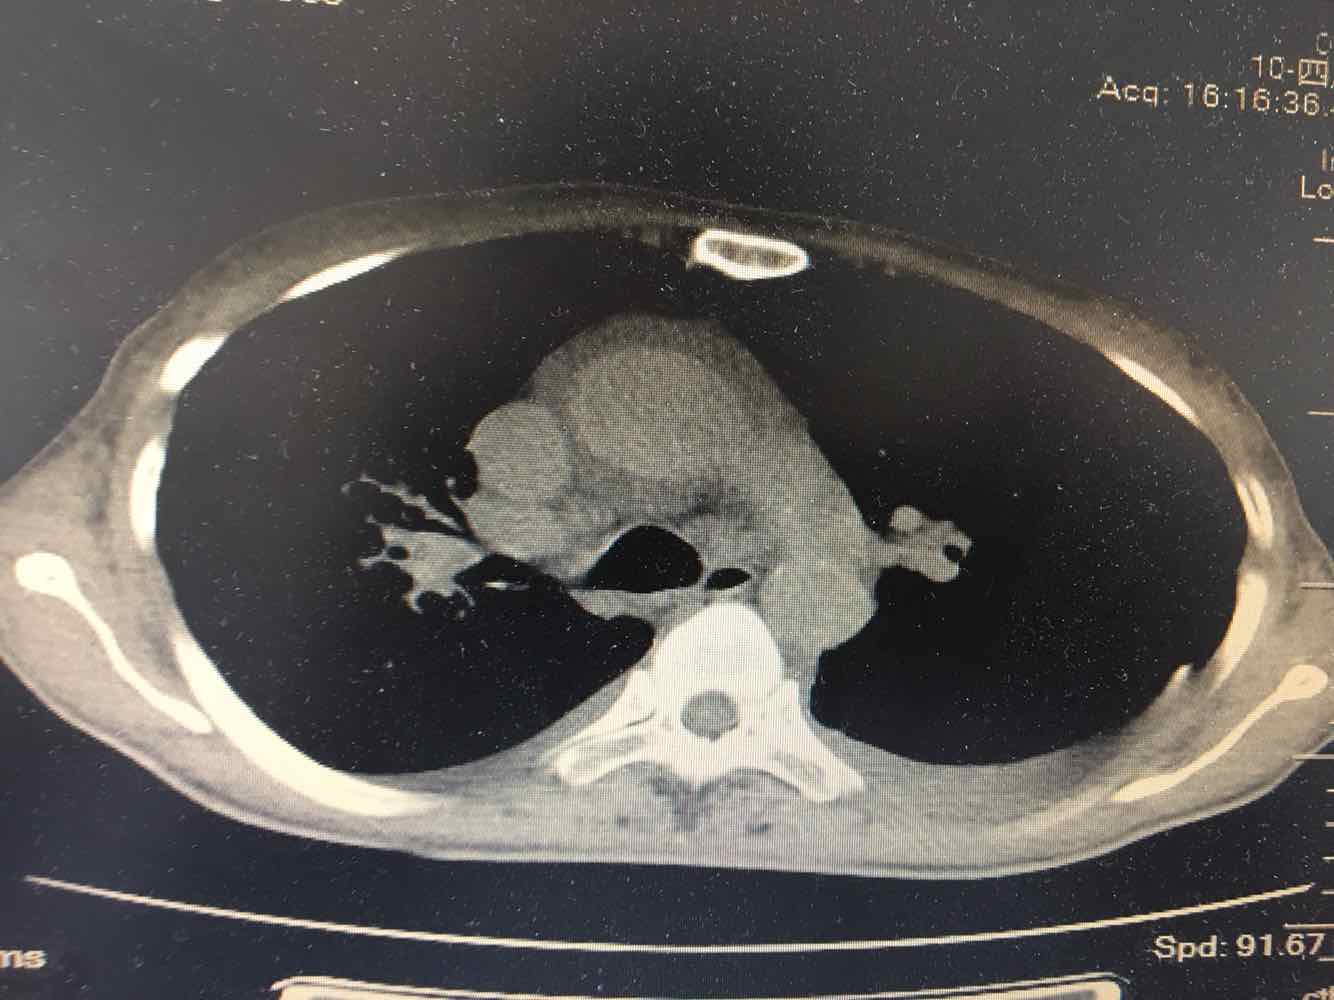

女,51岁,支气管扩张病史多年。慢性咳嗽咳痰喘息30年,加重1个月,无发热,气短为主,痰液不多,上腹不适,少尿。双肺干湿罗音。